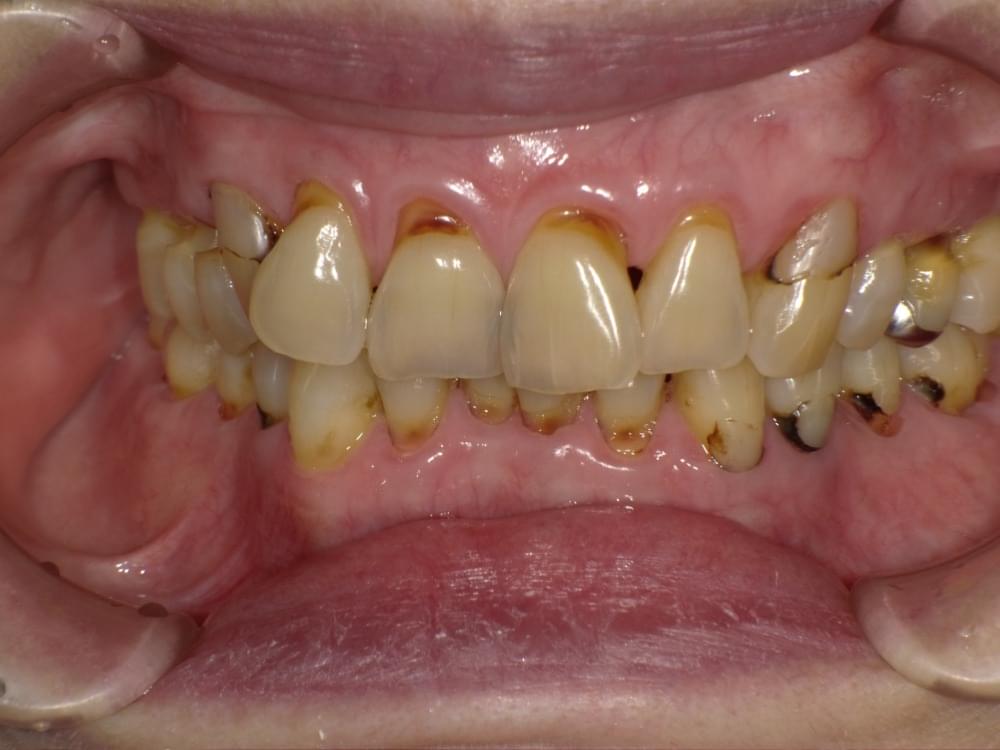

歯周病予防の為にセラミック装着を間違えると大変!!

こちらの写真の患者さんは上下前歯に沢山のセラミックをいれた直後から歯ぐきが良くならないとの理由で来院されました。

多くの時間をさいて歯ブラシとデンタルフロスをして頂いておりますが改善されておりません。

その原因は装着したセラミックにありました。

原因

① レントゲンで見るとセラミックが自分の歯よりも大きい

② 自分の歯とセラミックの境目にすき間が開いている

下矢印

③ ①と②の結果としていくら磨いても歯垢(プラーク)が取り除けない。